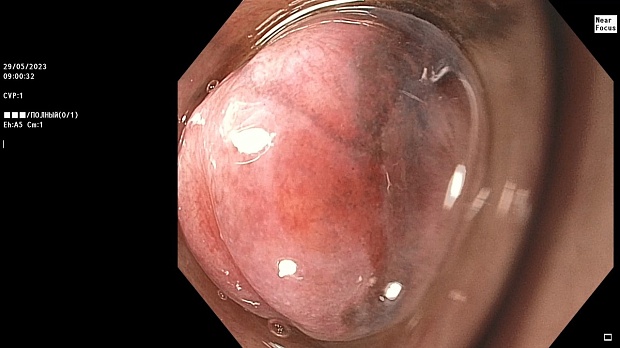

Иллюстрация №1: Эндофото. Сидероз нижней трети пищевода, осмотр в белом свете

Согласно полученным данным - в среднегрудном и нижнегрудном отделах пищевода определялась проксимальная граница плоских неправильной формы поверхностных рубцов суммарной протяженностью до 8,0 см. На этом фоне в зонах поверхностных рубцов по задней полуокружности визуализировались участки гиперпигментации в темный цвет (Рис. 1). При исследовании в режиме Dual Focus было отмечено наличие мелких (до 0,001 см) черно-коричневых включений, расположенных субэпителиально - в строме слизистой оболочки, сливания их в единый конгломерат не определялось (Рис. 2). При эндосонографии с применением минидатчика с частотой сканирования 20МГц выявлено, что все слои стенки четко дифференцируются, не утолщены, в слизистой оболочки визуализированы мелких гиперэхогенные включения с эхотенями (Рис. 3).